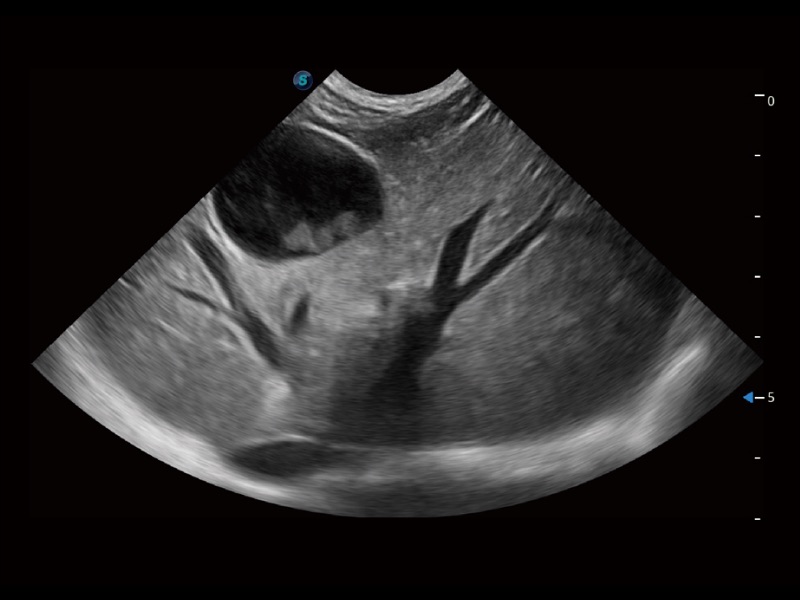

ProPet 70 进一步提升了微米成像算法,更加注重对基础原始图像的还原和保留,在有效减少斑点噪声、增强组织边界显示的同时,避免过度优化丟失真实的解剖信息。

大型犬、马科、农场动物及大型异宠动物

ProPet 70专为动物医生设计,对不同的动物体型和生理结构作出了针对性的优化。通过动物影像专用软件,可满足个性化的应用需求,帮助动物医生获得更精确的诊断数据。

ProPet 70 全新的动物超声智能软件和丰富的探头群,为动物医生提供了高清晰度和精细分辨率的图像,无论在宠物、马科、畜牧还是实验室动物等应用中都可以轻松应对,为您的日常工作带来满意的体验。